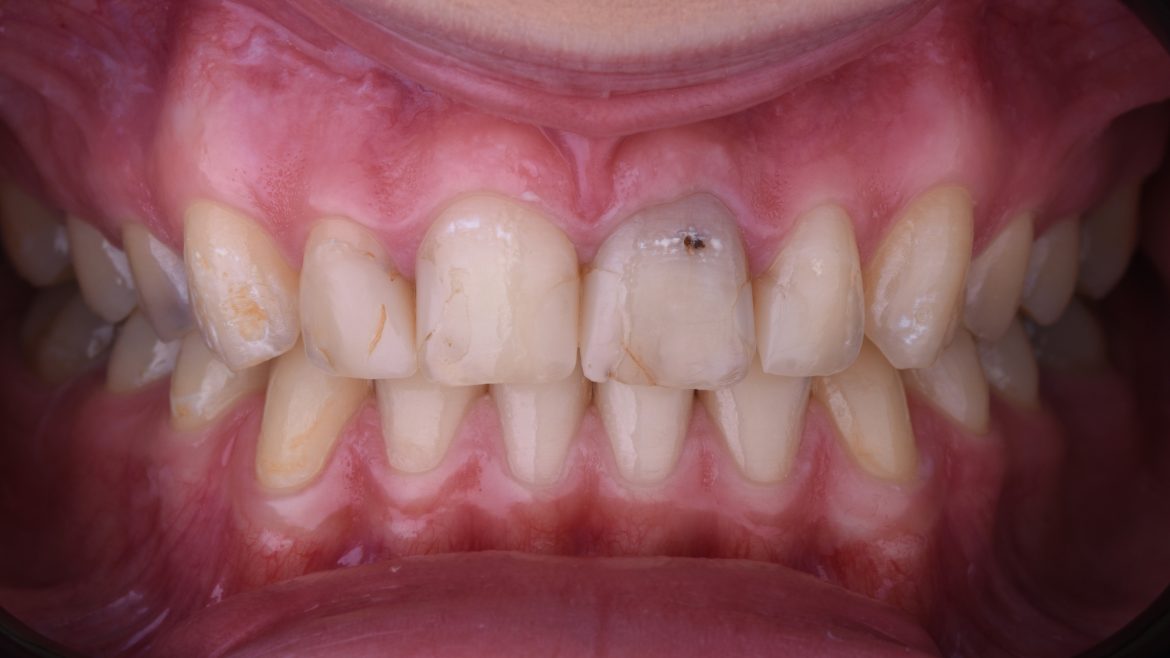

Naša pacijentkinja je mlada, ambiciozna, obrazovana devojka, dolazi kod nas sa željom da može slobodno da se nasmeje. Brz i efikasan tretman u njenoj situaciji doveo je do velike vizuelne promene. Keramički viniri i beljenje zuba bili su tretman koji je ona imala. Onog trenutka kada je dobila svoj novi osmeh, komunikacija već sa nama je bila drugačija. Sigurnost u sebe i lična satisfakcija je osećaj koji prati ove tretmane. Njen osmeh je tada postao njen zaštitni znak.